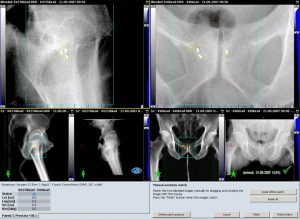

- OBI (On Board Imager): Dies ist eine bildgebende Kontrolle der Lagerung des Patienten durch eine Aufnahme von der Seite sowie von oben, die mit den knöchernen Strukturen des Patienten abgeglichen werden, wie sie sich bei der Therapieplanung darstellten. Abweichungen in der Lagerung werden im Bereich von 1 mm festgestellt und korrigiert. Die Behandlungsfelder können mit dieser Methode an jedem Tag exakt auf das Tumorareal angepasst werden. Besonders effektiv ist diese Methode, wenn Tumoren im Körper durch Clips markiert worden sind. Mit diesem Verfahren lässt sich dann nicht nur die knöcherne Kontur des Patienten, sondern ebenfalls die eigentliche Tumorlage feststellen.